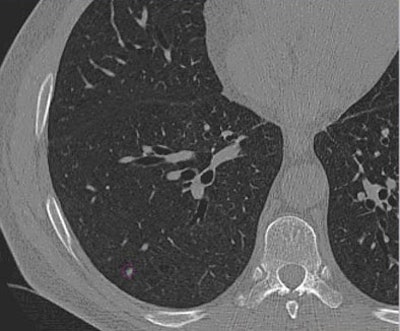

![]() |

| Images of solid lung nodules include uncompressed CT data (above), 24:1 compression (below), 48:1 compression (next down), and 96:1 compression (bottom). CAD detection performance of solid lung nodules greater than 4 mm in size did not suffer until 48:1 compression, and was found to be robust up to 96:1 even when the subjective visual appearance of the compressed images was degraded. The results suggest that 3D lossy wavelet compression can be performed without significant loss of CAD detection performance, which can minimize data storage and ultimately facilitate the implementation of CAD technology in a PACS environment. Images courtesy of Philippe Raffy, Ph.D. |